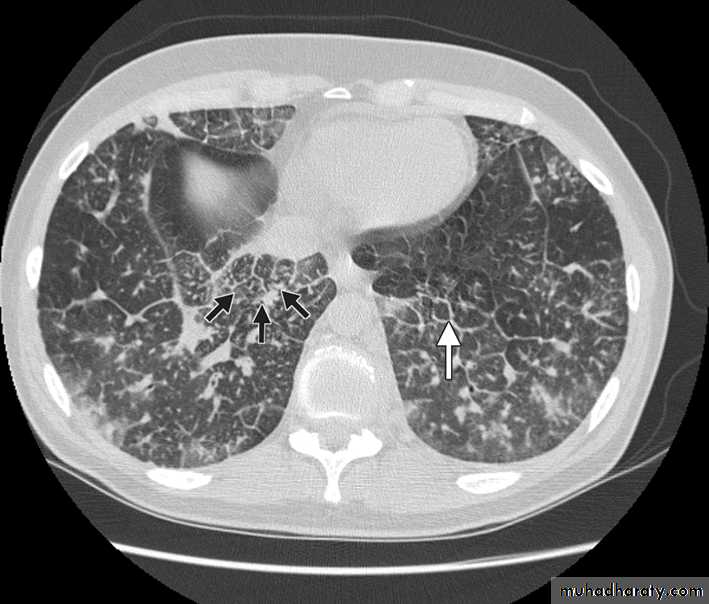

Chest CT scan shows multiple round nodules and masses of varying sizes in both lungs, consistent with metastases. There are also small bilateral pleural effusions.

Computed tomography scan showing nodular thickening of interlobular septa (white arrow), seen as polygonal arcades with thickened and nodular limbs, and ground-glass opacities (black arrows).

Lymphangitic carcinomatosis